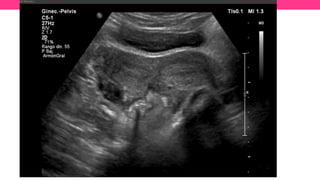

• #31 Patient 1. Ultrasound shows both hemi-uterus (A), with minimal distention of the left hemi-vagina